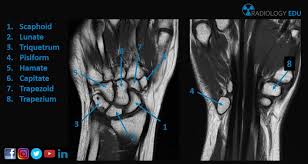

Carpal Bones Radiograph Labeled - Carpal Bones Mnemonic Anatomy Nursing And Medical Notes Basic Anatomy And Physiology Human Anatomy And Physiology Medical Knowledge : Carpi), are the eight bones of the wrist that form the articulation of the forearm with the hand.. The normal carpal bone angles were determined using the bone axes with the least observer variability (mean and range): Proximal row scaphoid lunate triquetrum pisiform. Swipe right for the answers! Start studying carpal bones labeling anatomy. The other four, superior or brachial, inferior or metacarpal , external or.

Carpal Bones Wikipedia from upload.wikimedia.org Drag the slider over the image to reveal or remove the highlighted bones of the radiograph labels: Only the proximal carpal bones are labeled and the distal ulna and radius. Pa radiograph of the wrist. Articulates with ulnar carpal bone. Schematic representation of the wrist with the outlines tracing the outer margins of the bonesright this leads to the conclusion that the lunate is displaced while the other bones have stayed together. They are usually divided into two rows: (a) distal phalanx 1st digit, (b) interphalangeal joint, (c) proximal phalanx 1st digit. Start studying carpal bones labeling anatomy.

Carpi), are the eight bones of the wrist that form the articulation of the forearm with the hand. The term carpus is derived from the latin carpus and the greek καρπός (karpós). Triangular appearance of lunate on frontal projection. Study the carpal bones as pieces of a jigsaw puzzleleft: Capitate and all other carpal bones lie posterior to lunate on lateral radiograph. The carpus is a composite joint composed of all the articulations to which the seven carpal bones contribute. Occurs when the lunate maintains normal position with respect to the distal radius while all other carpal bones are dislocated posteriorly. The carpal bones are the eight small bones that make up the wrist (or carpus) that connects the hand to the forearm. An easy and convenient way to make label is to generate some ideas first. The carpal bones are the eight bones of the wrist that form the articulation of the forearm with the hand. If an abnormal alignment of the carpal bones is depicted during imaging of the. Articulates with ulnar carpal bone. Dynamic instability is present if the carpal bones appear normal in standard radiographs taken at rest, but abnormal movement is identified in clinical examination, radiographic stress views, or cineradiography.

I Examination Of The Wrist Surface Anatomy Of The Carpal Bones Sciencedirect from ars.els-cdn.com They are usually divided into two rows: If an abnormal alignment of the carpal bones is depicted during imaging of the. Start studying carpal bones labeling anatomy. (a) distal phalanx 1st digit, (b) interphalangeal joint, (c) proximal phalanx 1st digit. The carpal bones, also known as the carpus (plural: Capitate and all other carpal bones lie posterior to lunate on lateral radiograph. The carpal bones are the eight bones of the wrist that form the articulation of the forearm with the hand. The distal row articulates with the bases of the metacarpal bones forming the pa hand radiograph above have the following structures labeled:

The carpal bones are a group of eight, irregularly shaped bones carpal bones labeled. Drag the slider over the image to reveal or remove the highlighted bones of the radiograph labels: